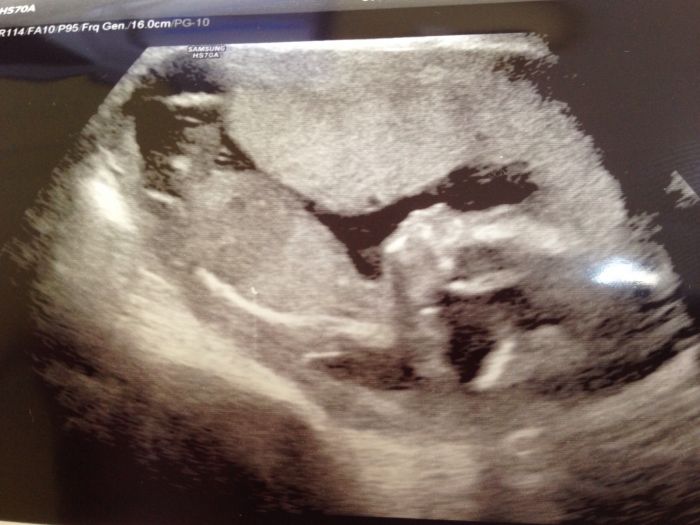

taky prikladam posledni foto

[889597] z tehle fotek sem mela radost

1.fotky kde mimi vypada jako mimi

a je tam hezky videt kde co ma